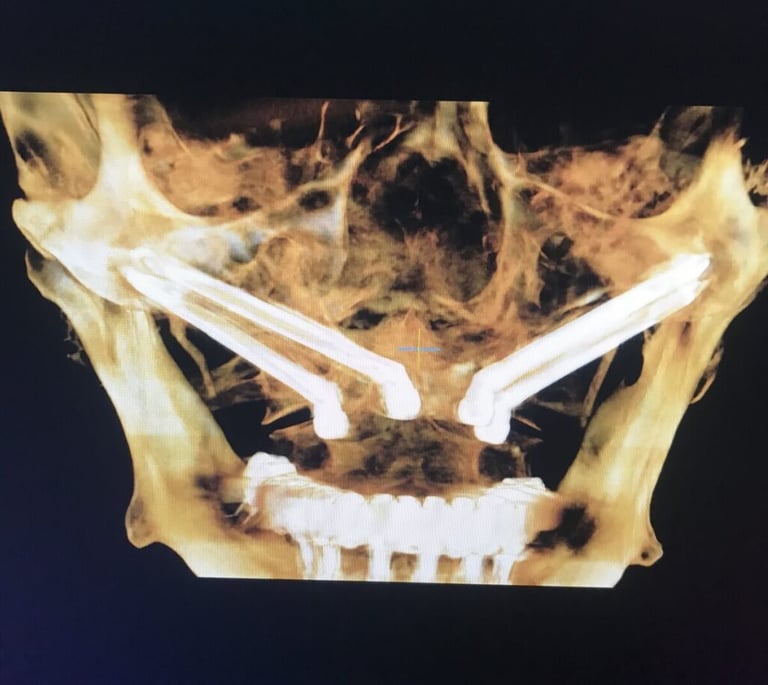

Zdjęcia dzięki uprzejmości prof. Paulo Maló. Prezentacja na forum korporacyjnym sponsorowanym przez Nobel Biocare na dorocznym kongresie Europejskiego Stowarzyszenia na rzecz Osseointegracji, Lizbona, 27 września 2019 r.

Chirurg umieszcza 4 tytanowe implanty w kości szczęki i/lub żuchwy w punktach zaplanowanych wcześniej na podstawie tomografii pacjenta.

IMPLANTY ZYGOMATYCZNE

W przypadku pacjentów z dużym zanikiem kości, optymalnym rozwiązaniem są implanty zygomatyczne (jarzmowe). Implanty jarzmowe różnią się od tradycyjnych implantów dentystycznych tym, że są zamocowane w kości jarzmowej (kości policzkowej), a nie w szczęce. Mają inny, wydłużony kształt i wymagają bardziej złożonej procedury. Jest to wspaniała alternatywa dla pacjentów, która radykalnie skraca czas rekonstrukcji uzębienia i umożliwia pacjentom cierpiącym na ciężką utratę kości szczęki powrót do normalnej jakości życia. W znakomitej ilości przypadków zęby mocuje się już w dniu zabiegu. Tym sposobem pacjent unika wielomiesięcznego cyklu inwazyjnych procedur przeszczepu kości w celu stworzenia podłoża dla konwencjonalnych implantów.

Przed umieszczeniem implantów jarzmowych wykonamy badanie TK, dzięki któremu specjalista implantolog precyzyjnie zaplanuje rozmieszczenie implantów. Następnym krokiem jest stworzenie strukturalnego modelu szczęki (tzw. szablonu), który pozwoli ocenić kształt Twojej kości policzkowej oraz szczęki i dokładnie przeprowadzić operację. Zabieg wszczepienia implantów jarzmowych zazwyczaj odbywa się w głębokim znieczuleniu, więc nie będziesz odczuwać bólu ani dyskomfortu. Nad przebiegiem operacji czuwać będzie zespół wyspecjalizowanych medyków z chirurgiem implantologiem i anestezjologiem na czele.